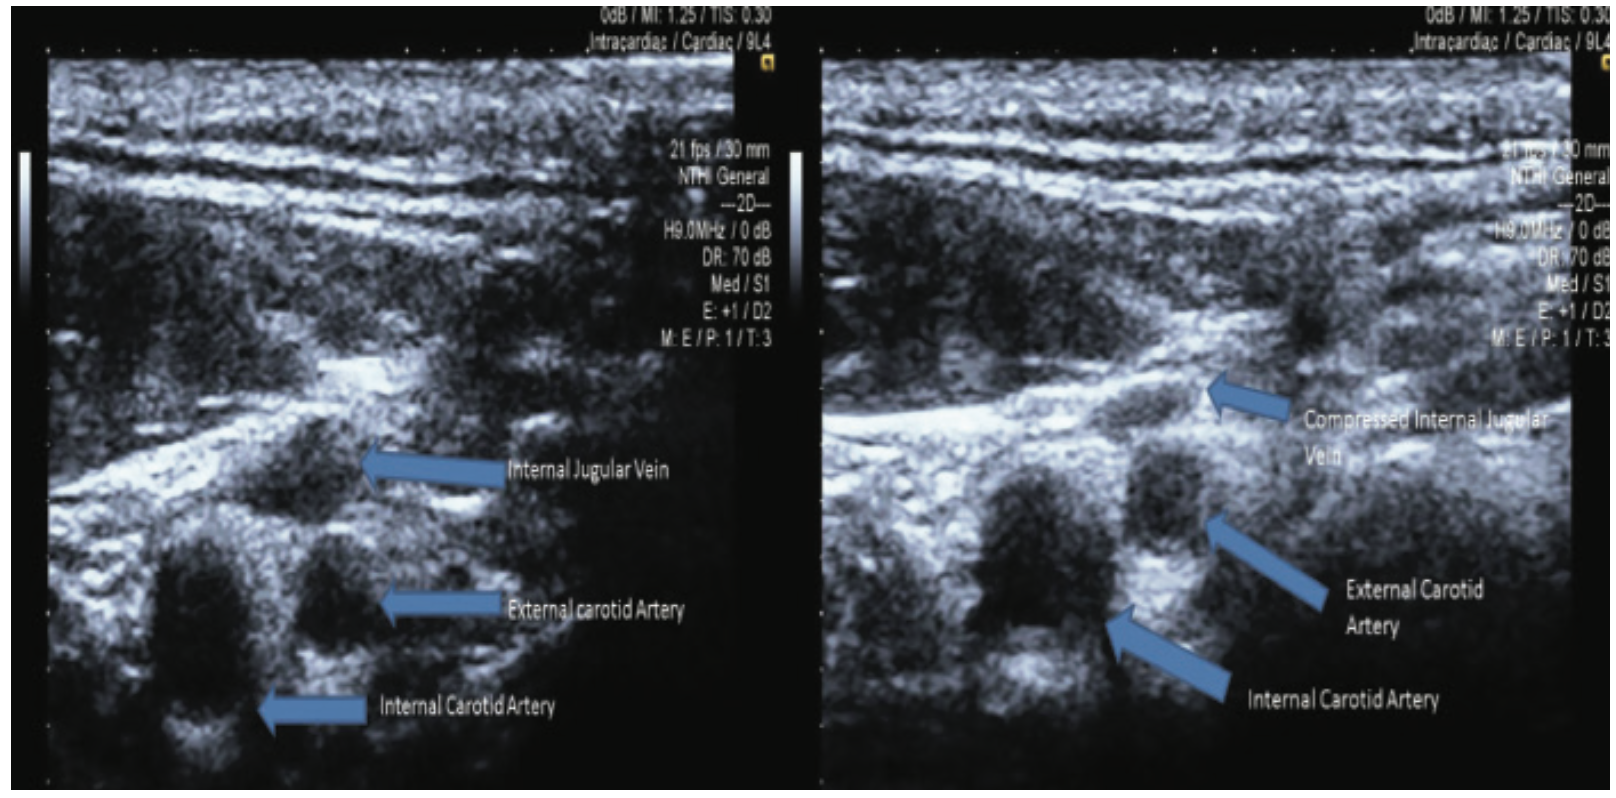

Jugular Vein Access

Evidence strongly supports US guidance for accessing the internal jugular vein.8 Ultrasound is important for jugular access, because of the proximity of the carotid artery, anatomic variations, and other structures in the neck.1,8,9 Research has also concluded that US guidance reduced jugular access complication rates, suggesting that US training can be used to curtail accidental internal carotid artery (ICA) puncture, local hematoma, and pneumothorax rates.9 Both short- and long-axis real-time US guidance approaches for internal jugular vein cannulation have proven to perform better than the landmark insertion technique for central venous catheters.10 Preliminary ultrasound evaluation of the vein patency, size and location should also be analyzed when attempting jugular vein access11 (Figure 7).